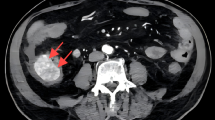

Invasive aspergillosis is most commonly seen in patients with immune disorders and usually in the lung. Local invasive aspergillosis of the gastrointestinal system is quite rare. A 13-year-old female without immune deficiency presented with acute abdomen due to full-thickness necrosis of the gastric fundus. The necrotic gastric wall was excised and the stomach repaired. The pathology revealed a gastric ulcer with invading Aspergillus hyphae and spores. Aspergillosis is an opportunistic infection and its spores cannot survive in the normal gastric mucosa. The Aspergillus spores in this case probably grew on a background of gastric ulcer and caused wall necrosis and that the surgical treatment possibly provided a cure because it remained localized to the gastric wall.